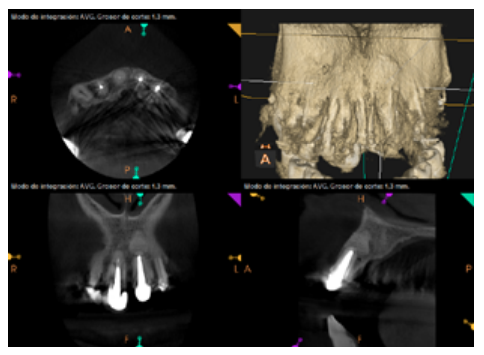

To confirm the endodontic origin and the size of the lesions, tomographic examinations were performed with a slice thickness of 75 microns using CBCT CS8100 (Carestream Dental™), in which radiolucent periapical lesions were observed at the level of 12, 11, 21 (with bicortical involvement), 25 and vestibular roots at 26 (Figures 4 to 8).

Six months later, the patient went for a check-up without any symptoms, both anteriorly and posteriorly. Periapical radiographs showed a decrease in the size of the pre-existing radiolucent periapical lesions (Figures 10 and 11). Given that the lesion on 25 remained to be treated, a control CBCT was performed where improvement at the level of 26 was verified (Figure 12), so microsurgery on 25 was scheduled.

After the microsurgery was performed on 25, the patient had no symptoms and the control tomographies at 12 months (in 25) and at 18 months in the remaining teeth showed regeneration of pre-existing radiolucent periapical lesions on all treated teeth (Figures 13 to 16).

Radiological checks were carried out at 6, 12 and 18 months using CBCT, which showed the absence of symptoms and a reversal of the chronic infection, as well as progressivity and stability in apical bone regeneration. At the level of 21, periapical radiopacity was observed, without loss of volume, and an absence of invasion of the space preserved by the surrounding soft tissue. Although some authors have used plasma rich in growth factors (PRGF) associated with Bio-Oss™ and Bio-Gide™ in cases similar to ours, we obtained adequate results without using PRGF as an additional technique13.